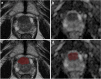

Objectives: To build a machine learning (ML) model to detect extraprostatic extension (EPE) of prostate cancer (PCa), based on radiomics features extracted from prostate MRI index lesions.

Methods: Consecutive MRI exams of patients undergoing radical prostatectomy for PCa were retrospectively collected from three institutions. Axial T2-weighted and apparent diffusion coefficient map images were annotated to obtain index lesion volumes of interest for radiomics feature extraction. Data from one institution was used for training, feature selection (using reproducibility, variance and pairwise correlation analyses, and a correlation-based subset evaluator), and tuning of a support vector machine (SVM) algorithm, with stratified 10-fold cross-validation. The model was tested on the two remaining institutions' data and compared with a baseline reference and expert radiologist assessment of EPE.